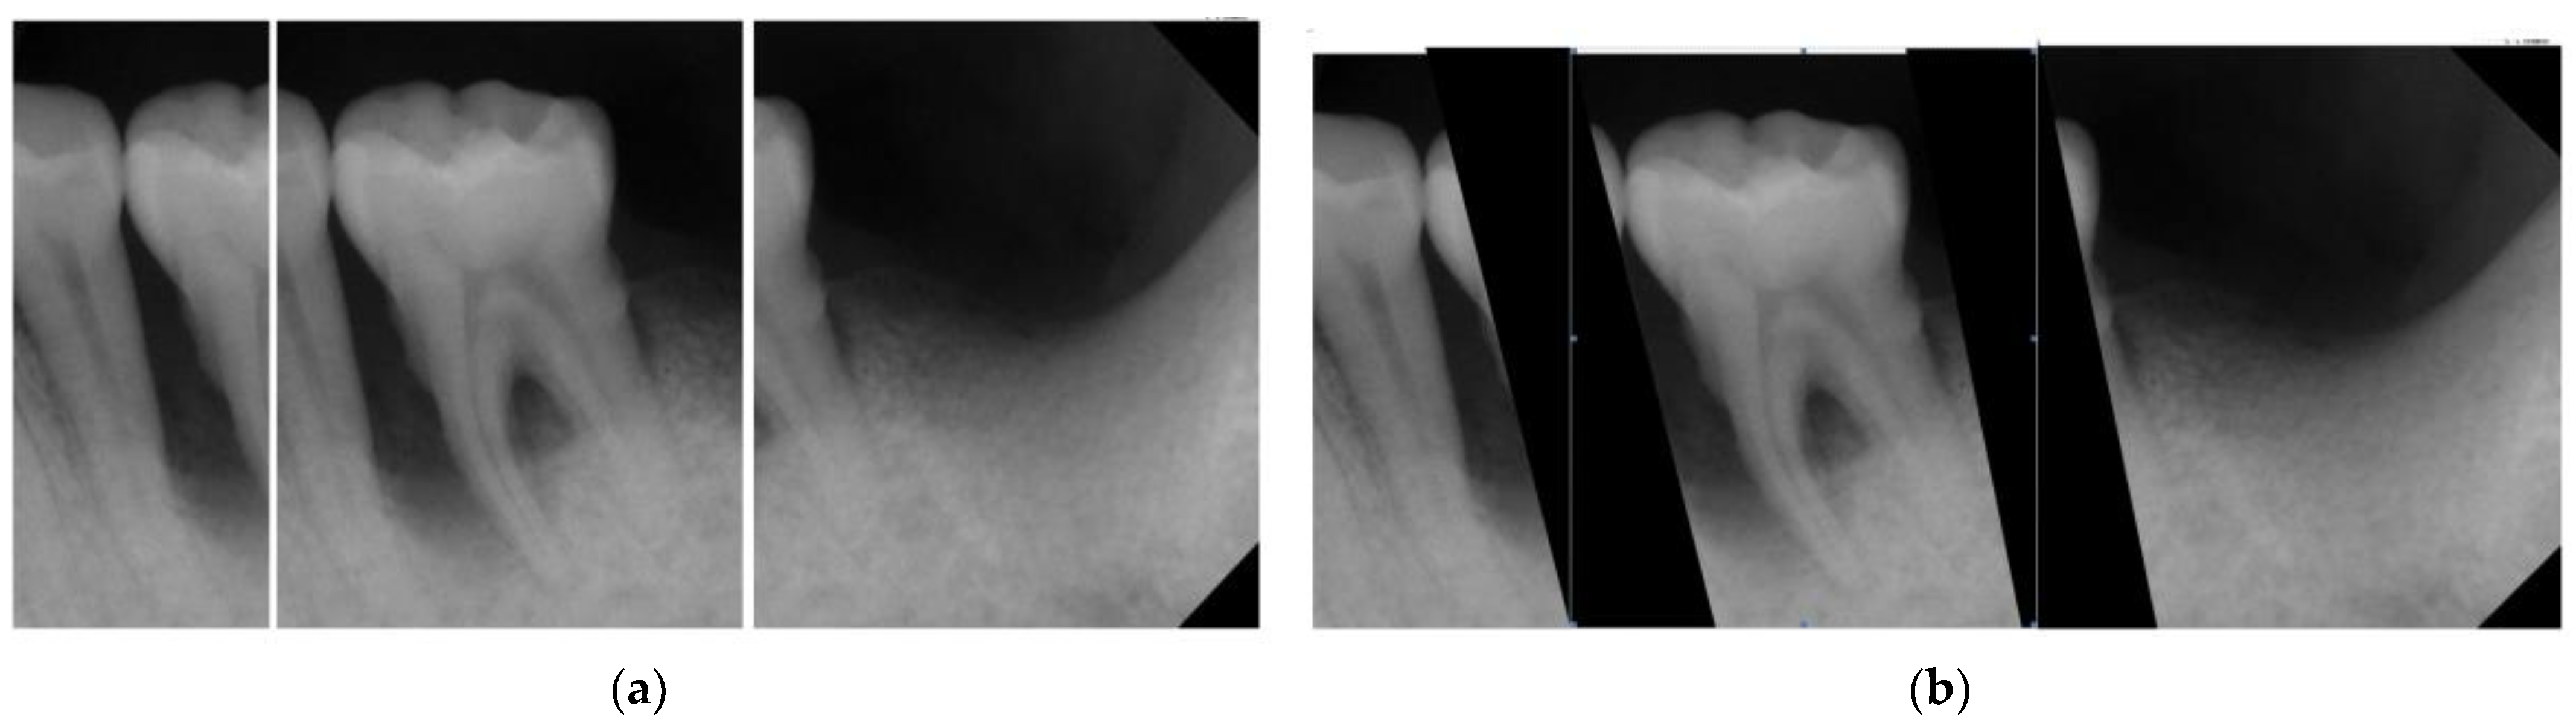

| Original Images | Gaussian High-Pass Filter | Gaussian High-Pass Filter + Mask | |

|---|---|---|---|

| Validation Accuracy | 84.16% | 87.21% | 94.97% |

| Validation Loss | 0.7634 | 0.4578 | 0.1822 |

| Model | GoogLeNet | GoogLeNet | GoogLeNet |

| Image | ![]() | ![]() | ![]() |